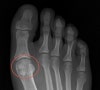

X-ray : 종자골 골절(Sesamoid fracture, Sesamoiditis)

AP view, lateral view, axial view 촬영을 시행합니다(가쪽 종자뼈는 oblique view에서 가장 잘 보입니다).

이분 종자뼈(bipartite sesamoid)가 정상이 변이형으로 존재하므로 골절과 감별해야 합니다.

정상적으로 25%에서는 선천적으로 종자뼈가 2분 혹은 여러 개로 갈라져 생기며, 이때는 불규칙한 경계를 보이는 골절과 달리 X-ray상 경계부가 부드럽습니다.